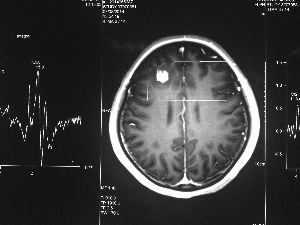

方框亮點為CT片顯示的異物

今年6月份,張敏在宿舍休息時,又發(fā)起了癲癇,也是口吐白沫,渾身抽搐。送到蘇州一家大醫(yī)院,頭顱核磁共振檢查出,張敏大腦右額葉處有一處病灶,也就是大腦額頭處有個東西。

腦袋里的東西,到底是腫瘤還是其他什么東西,這個謎像個石頭一樣,壓得張敏一家人喘不過氣。7月份,張敏一家又來到南京腦科醫(yī)院求醫(yī),第三次檢查后,醫(yī)生覺得很像是寄生蟲。不過,影像的檢查,只能作為醫(yī)生推測的依據,具體是什么,只有手術拿出來后才能知道。

8月14日,張敏上了手術臺進行開顱手術。術中,楊坤將白色像棉線一樣的異物夾出來后,最初還沒有意識到是什么東西。“放在手術臺上的時候,它竟然動起來了,我當時就想到,這是寄生蟲?!睏罾ふf,“我們量了一下,蟲子有3厘米長?!?/p>